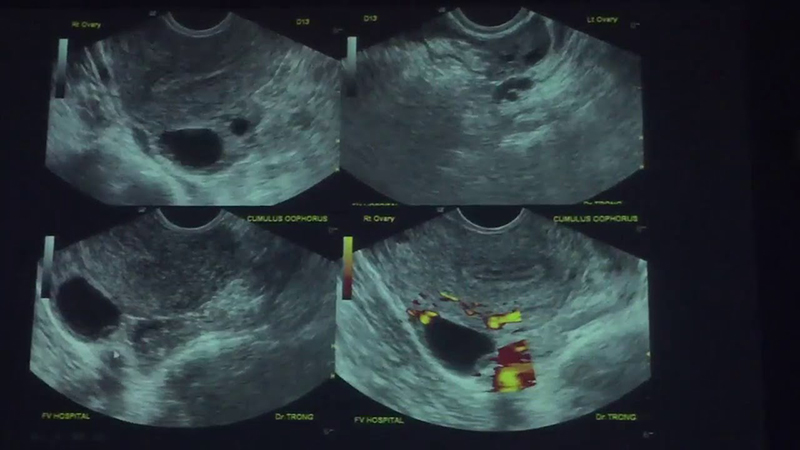

Chào bạn của Chuyenseg, chị biết có rất nhiều bạn nữ đang thắc mắc về chu kỳ của mình, đặc biệt là việc trứng đã rụng siêu âm có thấy không. Đây là một câu hỏi rất hay và quan trọng, nhất là khi chúng ta muốn hiểu rõ hơn về cơ thể mình, hoặc […]